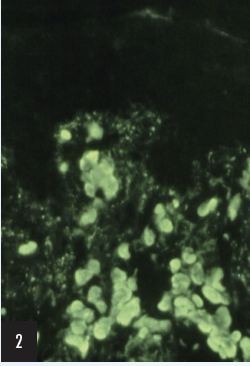

2. The fluorescent structures are:

a)  Civatte bodies

These upper dermal structures are Civatte bodies (also known as cytoid or hyaline bodies), which are probably remnants of apoptotic keratinocytes coated with immunoglobulins. They may stain with antisera for IgG, IgA, and/or IgM. They may be seen in the upper dermis in a variety of inflammatory conditions. Civatte bodies are not disease specific but often are present in large numbers in lichen planus.